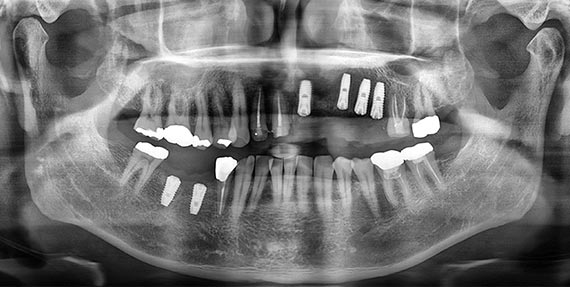

3차원 CT 이미지와 컴퓨터 모의 시술 기법을 통해 환자 턱뼈에 보다 정확한 위치에 식립하는 시술 방법으로, 시술 전 미리 위험 요소를 피할 수 있습니다. 잇몸에 작은 구멍만 뚫어 진행되기 때문에 큰 절개 없이 최소 통증으로 시술 받으실 수 있습니다. 동탄주치과에서는 Osstem Oneguide 분석 시스템을 통한 네비게이션 임플란트를 시행하고 있습니다.

모의수술의 정보를 토대로 가이드를 제작하고 가이드에 기반한 정확도 높은 수술을 진행합니다.

시술 전후 비교

BEFORE

AFTER